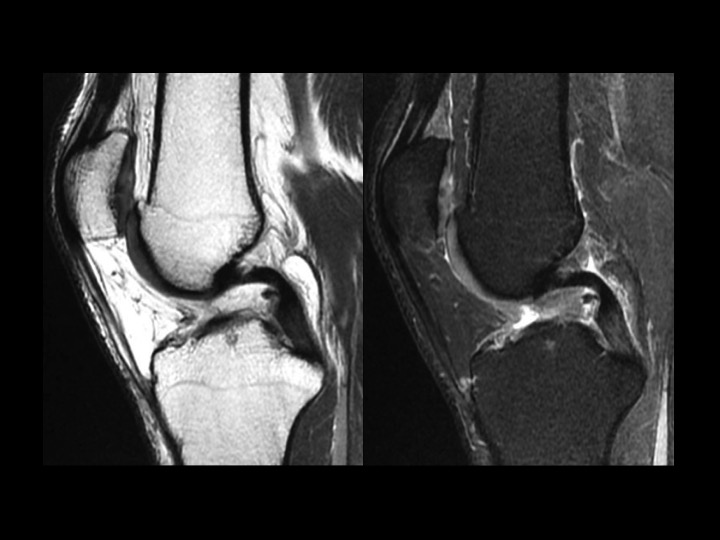

35M pain and swelling 1 month after fall playing basketball

There is intermediate signal soft tissue thickening along the medial aspect of the PCL with what appears to be a tear near the tibial insertion of the posteromedial bundle in the Sag images. The larger anterolateral bundle is intact, with minimal increased intrasubstance signal in the vertical segment. This is an isolated injury, so it will certainly be treated conservatively. I know there has been controversy over soft tissue thickening in this location, with reports of synovial thickening/scarring with intact PCL. Note that the opposite knee does not look like this (image 5). Even though this should heal with stability, I wonder if this might be the cause of scarring we sometimes see in this location and if it might not be a source of chronic pain and limitation. Thoughts? Reference article.

posteromedial bundle of posterior cruciate ligament ( RID2786 )